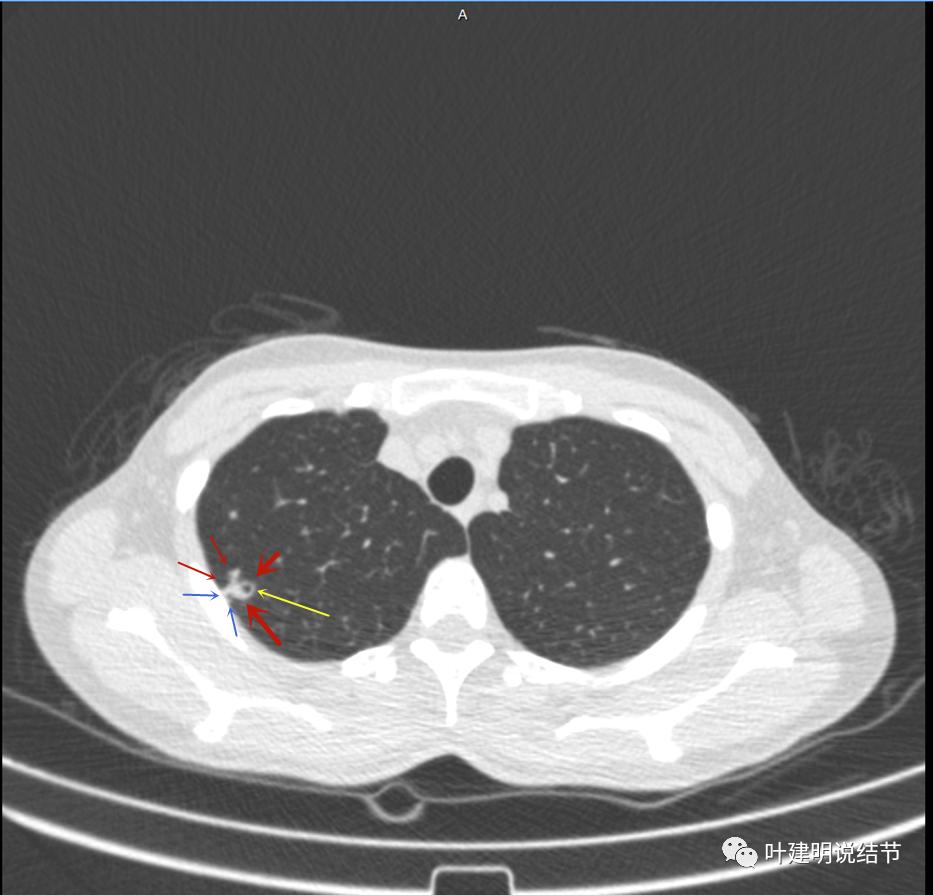

病灶有空洞(黄色箭头),主病灶边上见条索状高密度影(细红色箭头),邻近胸膜有粘连(蓝色箭头)

邻近胸膜明显增厚,且广基底,主病灶前方有小片磨玻璃影

主病灶与胸膜间基本相连,模糊清(蓝色箭头),主病灶壁厚薄欠均,边上有高密度条索状(桔色箭头)